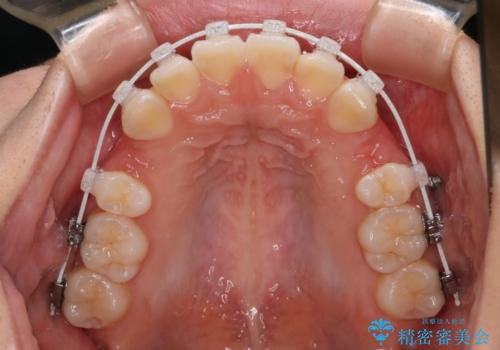

- 矯正装置

- 審美装置